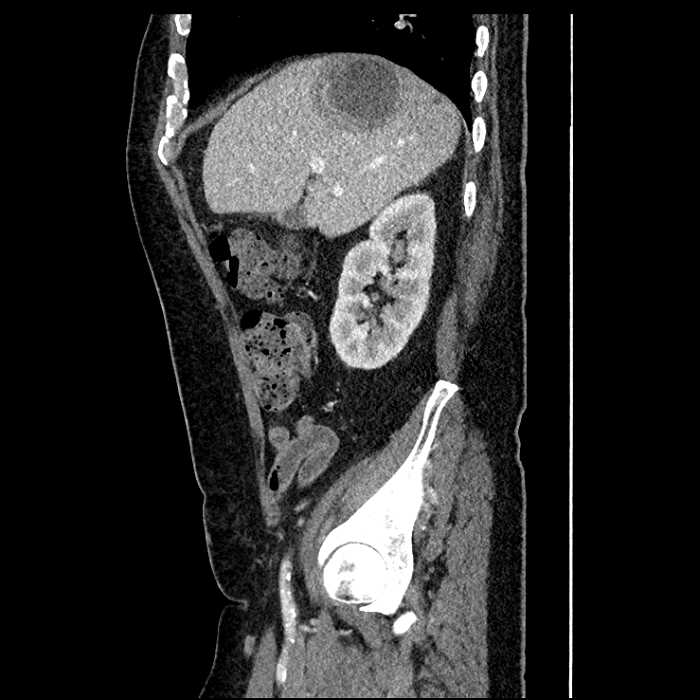

• Large fluid density structure in hepatic segments 7 and 8 measuring 10 x 7 x 7 cm with internal septation and circumferential ill-defined low density compatible with edema

• Peripherally enhancing subcapsular collections along the anterior margin of the left hepatic lobe measuring 3 x 1 cm and 2 x 1 cm

• Clearly marginated fluid density structure in segment 7 and several other scattered tiny hypodensities, which likely represent cysts

Acute sigmoid diverticulitis complicated by a small contained perforation and a large abscess in the right hepatic lobe. Additional small subcapsular abscesses along the anterior margin of the left hepatic lobe.

• The classic CT imaging appearance is a double target sign with internal low density surrounded by an internal enhancing rim (capsule) and a low density external rim (edema)

Hepatic abscess showing the double target sign with low density internally surrounded by a thin inner enhancing rim (red arrow) and ill-defined outer low density rim (yellow arrow). Blue arrow indicates an internal septation. Red arrows: additional smaller subcapsular abscesses. Red arrow: focal contained perforation associated with diverticulitis.